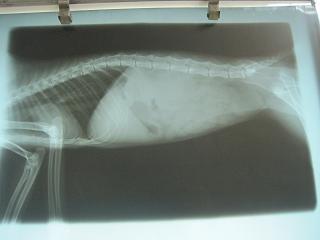

- 編號: 435

主題: 嚴重肝病導致抽筋的貓 申請者姓名: 敏大哥 花色: 申請日期: 2012-06-18 23:25:39 申請者部落格: 申請者臉書網址: 所在縣市/合作醫院: 台北市/詠欣動物醫院 治療費用: 1900元 需求人數: 5人 已結案 (2012-12-01 20:05:42) 報名人員: 潘逸群(已付款)、WeiLin Chen(已付款)、Huang Emma(已付款)、楊宸(已付款)、吳柏毅(已付款)、 候補人員: 小舟、 動物病情說明: 這是幫張媽媽po的.貓咪這1-2天精神不濟的窩在牆角.又忽然神情異常的狂跳.送院檢查發現有嚴重肝病導致抽筋 和球蟲引起的腸子發炎.經過一天緊急治療,仍舊不治..